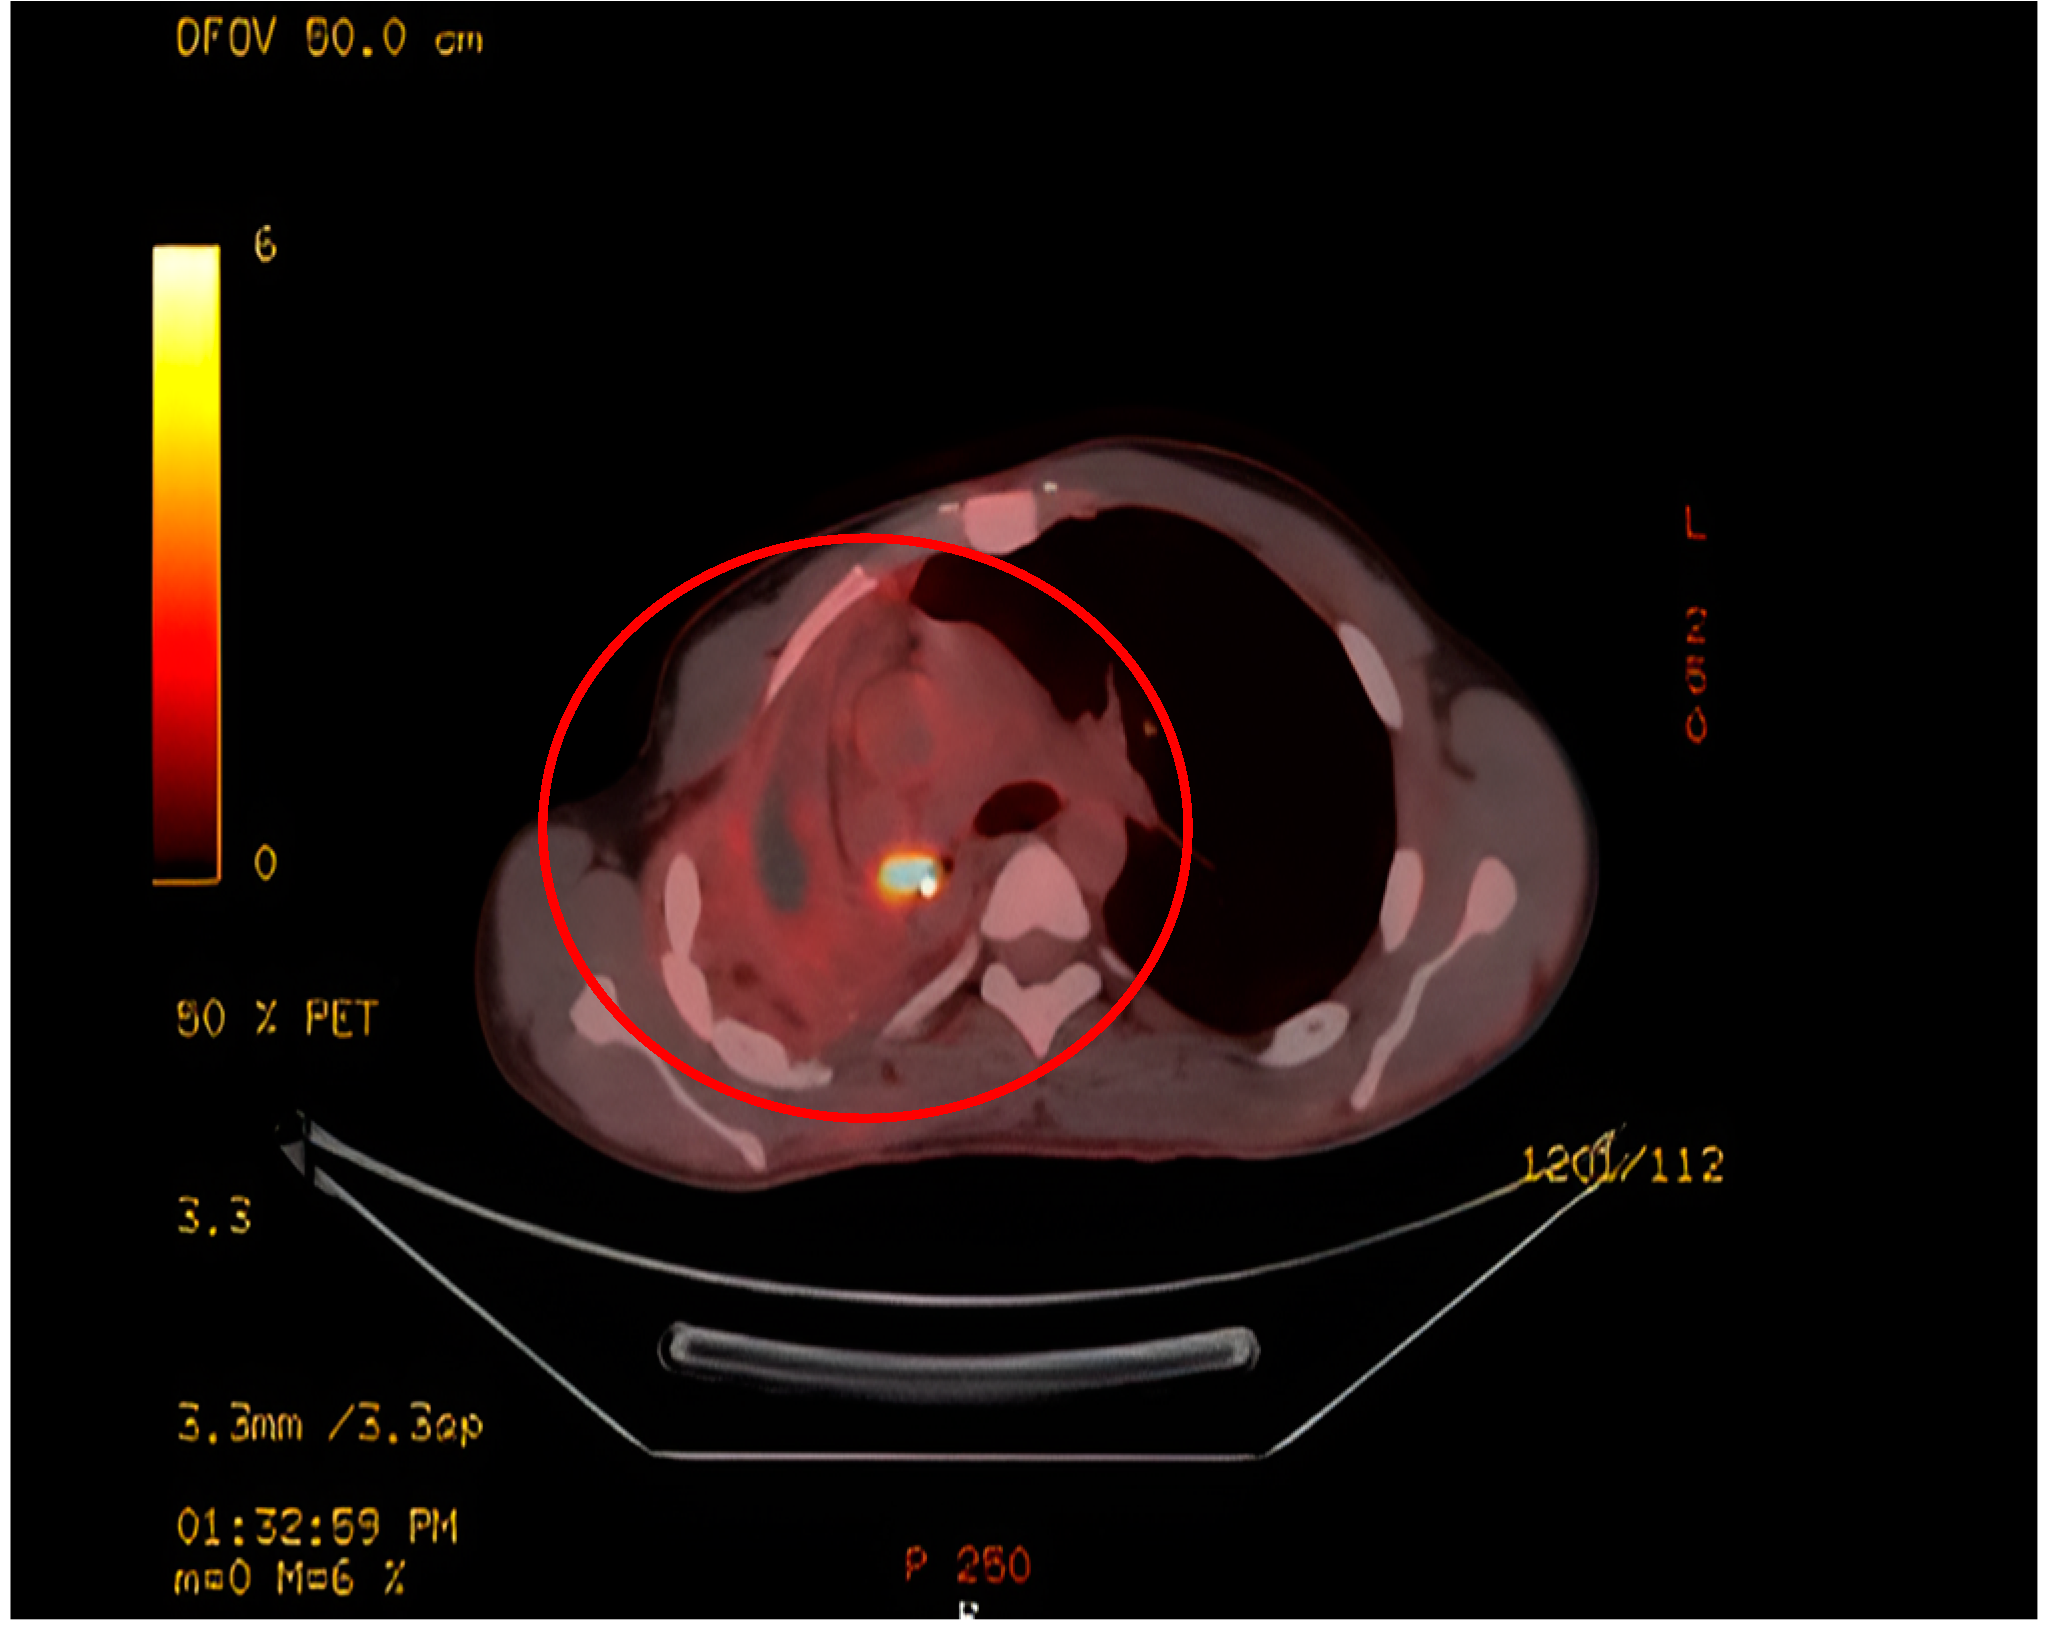

Upon evaluation at our institution, a chest radiograph displayed a sizable homogenous opacity in the right inferior mediastinum, prompting the ordering of a PET scan. The PET scan unveiled a hypermetabolic lesion located in the right main bronchus, as illustrated in Figure 1. Subsequent examination via flexible bronchoscopy exposed a fistula in the right bronchus intermedius and an elongated bronchial stump on the right side extending towards the secondary carina. Despite these findings, the patient's general clinical examination was unremarkable.

Radiologically, IMTs present with variable and nonspecific features depending on their location [14]. On CT, Pulmonary IMTs show heterogeneous enhancement and may be associated with atelectasis and/or pleural effusions. Amorphous or dystrophic calcifications in pulmonary IMTs are frequently present, usually in children more than adults [15, 16]. MRI can reveal heterogeneous signal intensities, and FDG-PET scan demonstrates high uptake [14]. In this case, there was intense FDG uptake noted in a circular pattern beneath the right main bronchus.

Figure 1. PET scan shows a hypermetabolic lesion around the right bronchial stump.